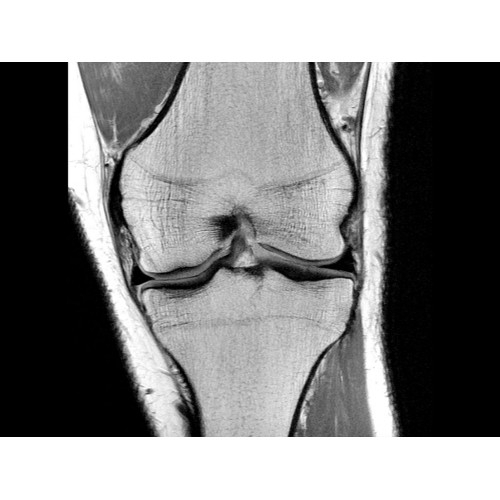

• РЧ-катушки, оптимизированные для исследования конкретных участков тела — элементы катушек высокой плотности располагаются вокруг исследуемых участков тела и при необходимости обеспечивают расширенный охват и оптимальное качество изображений при каждой процедуре.